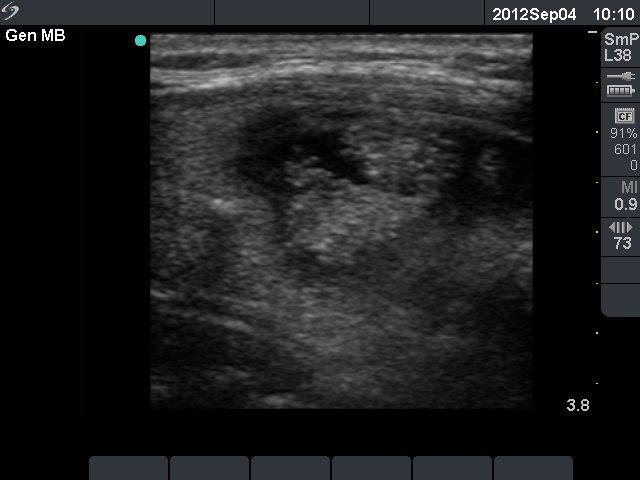

Benign cystic-colloid goiter (cytological diagnosis)

There are several pale granules and lines in the solid part of the nodule (left image), while the right image demonstrates the presence of posterior back wall enhancement figure in the dorsal wall of the small cystic areas.